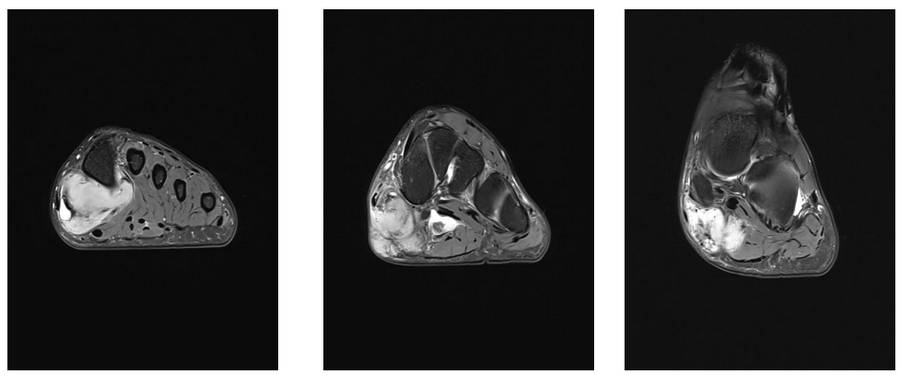

Ameliyat Öncesi: MR’da ayak medialde sınırları düzensiz heterojen kitle görülmekte